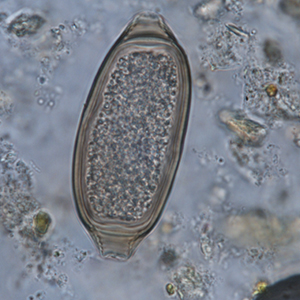

Whipworm eggs are oval, symmetrical and have a barrel-like shape. They measure 50 to 80 µm long and 20 to 40 µm large. They have a regular and smooth outer membrane. Protruding polar plugs are present at either tips of the parasite, and they are linked to the egg by a striated insertion site. Ridges of this insertion site are perpendicular to the axis of the egg. It is impossible to distinguish species of whipworms by ovodiagnosis only (Garcia, 2021).

- Capillarid eggs have more of a sausage-like shape whereas whipworm eggs are barrel-shaped. This criterion may be difficult to identify on coproscopy.

- Polar plugs of capillarid eggs are flatter than those of whipworm eggs. However, polar plugs of whipworm eggs can become flat if the eggs have spent a long time in the environment and are slightly degraded.

- Capillarid and whipworm eggs have polar plugs which are linked to the egg by a striated insertion site. In capillarid eggs, ridges are parallel to the axis of the egg, whereas they are perpendicular to the axis of the egg in whipworms. This is the main element to consider when trying to differentiate the two types of eggs.

Iris (Iris spp.) pollen seeds are also included in the differential diagnosis for whipworms. These pollens have the same elongated form and are of the same size as whipworm eggs. However, their outer membrane is thinner, and their poles are less distinguishable. Moreover, their content is more heterogeneous (Petithory et al., 1995).